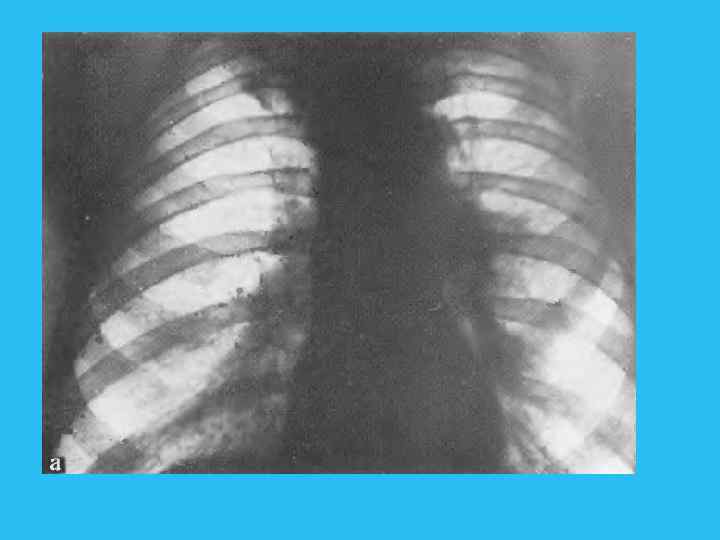

Рентгенологическая семиотика Рентгенологическая картина центрального рака обусловлена: самой опухолью; возникающим нарушением бронхиальной проходимости; осложнениями, развивающимися в связи с прогрессирующим ростом опухоли и метастазами. Преимущественно эндобронхиальный (внутрь) рак Рассматривая рентгенологическую симптоматику и клиническую картину эндобронхиального рака с момента его возникновения, следует выделить определенные фазы его развития (табл. 5). Первая фаза соответствует минимальным размерам опухоли, когда клиническая и рентгенологическая картины не дают оснований для постановки диагноза. В этой фазе отсутствуют клинические симптомы, рентгенологически тень опухоли или ее косвенные признаки не определяются. Дальнейший рост узла приводит к сужению бронха и нарушению вентиляции сегмента, что указывает на существование опухоли, хотя сама по себе она рентгенологически не видна. Наступает вторая фаза развития опухоли, которая проявляется гиповентиляцией сегмента, отражающей стадию нарушения бронхиальной проходимости. Сужение просвета брон хиальной ветви приводит к недостаточному поступлению воздуха в дрени руемый сегмент легкого. Последний на фоне воздушного легкого приоб ретает несколько меньшую прозрачность, сосуды его сближаются, что свя зано как с меньшим поступлением воздуха в этот сегмент, так и с расши ренном кровеносных сосудов. Возникает застойная гиперемия ввиду понижения внутриальвеолярного давления (рис. 227).

Возникает застойная гиперемия ввиду поннжения внутриальвеолярного давления (рис. 227). Развивается сегметарная гиповеитнляция, которая наиболее отчетливо улавливается в фазе максимального вдоха. Поэтому обычным рентгенологическим приемом при просвечивании должно быть детальное изучение воздушности легких в фазе задержанного глубокого вдоха. В этой стадии при резком вдохе можно заметить толчкообразное смещение органов средостения в больную сторону (положительной симптом Гольцкнехта — Якобсона). При сегментарных поражениях этот симптом может быть неясно выражен и его отсутствие не позволяет снять подозрение на нарушение бронхиальной проходимости. Следует провести также пробу кашлевого толчка (по А. Е. Прозорову), который иногда вызывает более выраженное толчкообразное смещение средостения в сторону поражения в связи с меньшим давлением в гиповентилируемом сегменте легкого. В этой I стадии нарушения бронхиальной проходимости большое значение приобретает тщательный анализ легочного рисунка. Некоторое сгущение сосудистого рисунка, связанного с расширением сосудов, небольшое объемное уменьшение пораженного сегмента из за гиповентиляции по сравнению с противоположной стороной должны заставить подумать о нарушении бронхиальной проходимости.

Рентгенологически проявлением этой стадии является сегментарное вздутие, которое развивается по мере дальнейшего роста опухоли и суже ния просвета бронха. Поскольку в фазе выдоха просвет бронха суживается, происходит накопление остаточного воздуха в сегменте и его прогрессирующее вздутие. Эта фаза нарушения бронхиальной проходимости лучше прослеживается в фазе максимального выдоха (рис. 228). Рис. 228. Обеднение сосудистого ри сунка в правом легком. Прямая рентгенограмма. а — фаза вдоха; б — фаза выдоха: вздутие правого легкого» смещение средостения влево.